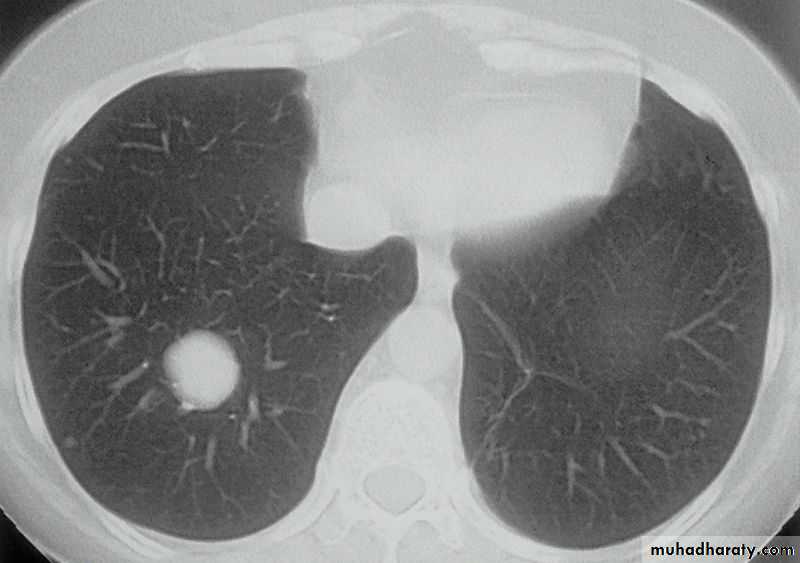

Differential diagnosis?